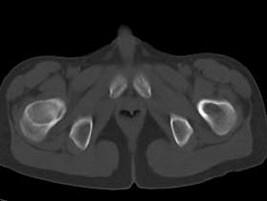

问题 男,13岁,右髋部疼痛不适,无红肿,请结合所提供的图像,选择最佳答案 ( )

选项 A、内生软骨瘤 B、骨纤维结构不良 C、骨巨细胞瘤 D、畸形性骨炎 E、非骨化性纤维瘤

答案 B